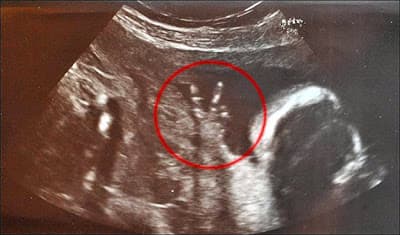

Imagen de ultrasonido de un bebe(feto) de 23 semanas de gestación que revela en sus dedos una señal de amor y paz. Gran señal de quien prepara camino para crecer como un luchador y representante de la paz y amor en el mundo. No se si la fot

Imagen de ultrasonido de un bebe(feto) de 23 semanas de gestación que revela en sus dedos una señal de amor y paz.

Gran señal de quien prepara camino para crecer como un luchador y representante de la paz y amor en el mundo.

No se si la foto es real, si existe photoshop, no puedo garantizar la autenticidad de la misma. Lo que si es examen aprobado es el buen dato de la instantánea, como para un buen anuncio o campaña.